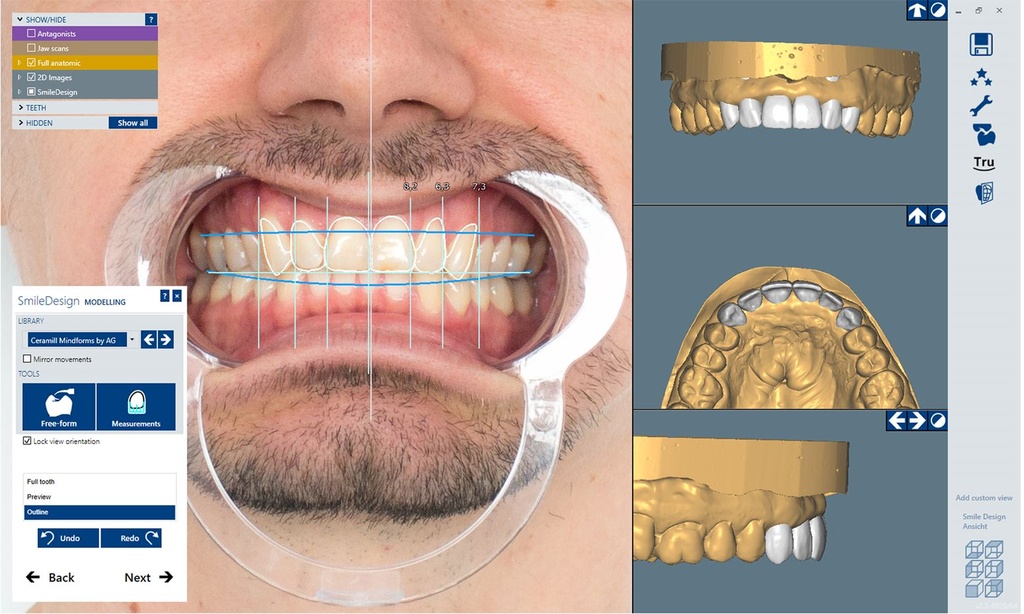

AM179704The new Software upgrade Ceramill M-Smile in combination with the Ceramill Mind design software now allow the esthetic planning, 3D design and production to be modeled in a continuous digital workflow. By starting the digital design process with the esthetic planning with Ceramill M-Smile the range of indications goes far beyond a mock-up and allows to use smile design as starting point for any type of digital dental indication.

For the visualization of the esthetic planning the additional module Trusmile is needed.

- Increases the satisfaction and acceptance of the patient by transferring esthetic planning into real life pictures

- Simplifies the esthetic planning based on the facial proportions through intuitive tools and workflows

- Automatic transfer into 3D design and seamless integration into the wizard guided Ceramill workflow for maximum comfort